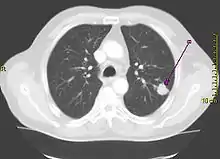

Performing a chest radiograph is one of the first investigative steps if a person reports symptoms that may be suggestive of lung cancer. This may reveal an obvious mass, the widening of the mediastinum (suggestive of spread to lymph nodes there), atelectasis (lung collapse), consolidation (pneumonia), or pleural effusion.[7] CT imaging of the chest may reveal a spiculated mass which is highly suggestive of lung cancer, and is also used to provide more information about the type and extent of disease. Bronchoscopic or CT-guided biopsy is often used to sample the tumor for histopathology.[17]

Lung cancer often appears as a solitary pulmonary nodule on a chest radiograph. However, the differential diagnosis is wide. Many other diseases can also give this appearance, including metastatic cancer, hamartomas, and infectious granulomas caused by tuberculosis, histoplasmosis or coccidioidomycosis.[66] Lung cancer can also be an incidental finding, as a solitary pulmonary nodule on a chest radiograph or CT scan done for an unrelated reason.[67] The definitive diagnosis of lung cancer is based on the histological examination of the suspicious tissue[1] in the context of the clinical and radiological features.[6]